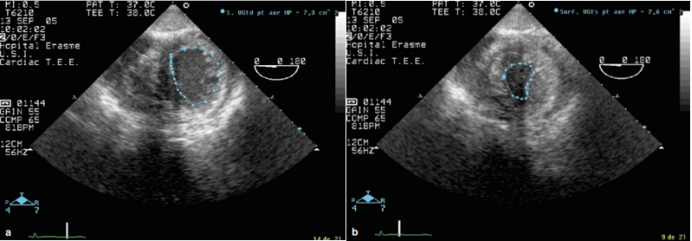

超声检测心包积液的能力取决于积液的大小和在不同超声视窗的分布,较大的积液导致心脏周围可见的无回声空间。通过长轴切面,可以检测到少量后心包积液;通过心尖四腔切面,可以评估右心房、右心室游离壁的运动(图4)

图片

4  心包积液的超声检测(*区域为心包积液)

心脏压塞的超声诊断:包括右心腔在吸气时增大的比例下降、右心房收缩期塌陷、右心室游离壁在舒张期塌陷、下腔静脉内径增宽呼吸变化率减低(视频1,图5)。右心房的收缩期塌陷是早期心脏压塞的一个敏感标志,早期阶段敏感性为50%,晚期阶段敏感性可达100%。然而,在右心室充盈压力升高的患者中,如由肺动脉高压或高血容量引起,跨膜压力可能需要更高才能导致心房塌陷,从而降低压缩效应。